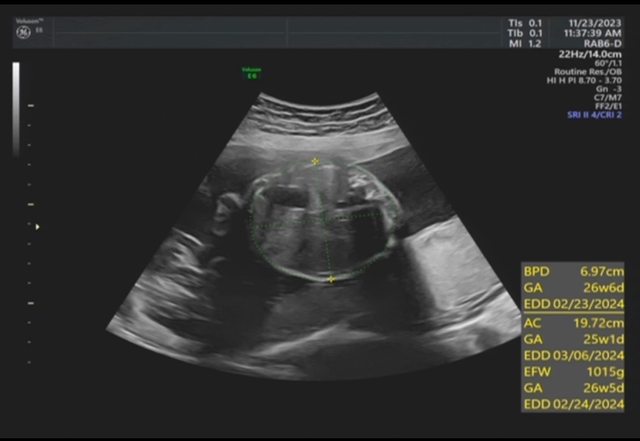

昨天去產檢,醫生覺得寶寶的胃偏大之後要注意觀察 我搜尋了一下好像只有看到胃太小的文,請問大家有沒有遇過類似情況? 我後來看了一下22週的高層次照片,那時候寶寶也是胃大大的,但那時只說是寶寶可能剛 吃飽 https://i.imgur.com/amlKp09.jpg

每一胎的狀況真的不一樣,這次第二胎先歷經羊水少週數小三週,到現在追到剩小一週, 但昨天醫生又提醒胃好像偏大,只希望二寶可以健康平安出生~ -- ※ 發信站: 批踢踢實業坊(ptt-website.tw), 來自: 101.12.24.40 (臺灣) ※ 文章網址: https://ptt-website.tw/BabyMother/M.1700797726.A.8D2